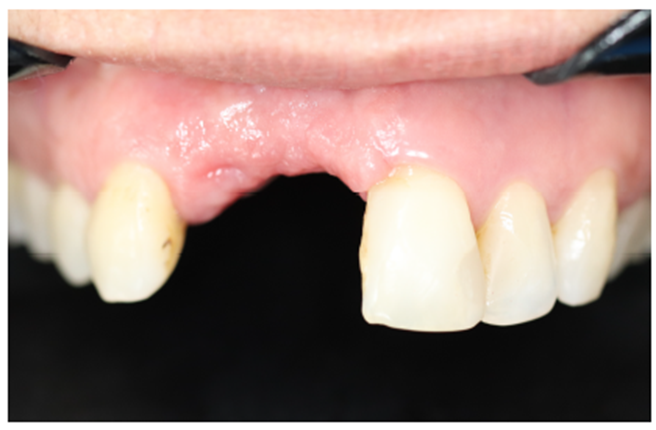

Paciente do gênero feminino, 46 anos, Leucoderma. Compareceu à clínica odontológica com a queixa de dificuldade na mastigação e instabilidade de sua prótese parcial superior.

Ao exame clínico observou-se a ausência parcial dos dentes na maxilar e uma prótese parcial removível nos dentes 21 e 22, com extenso defeito em rebordo alveolar (Figura 1).